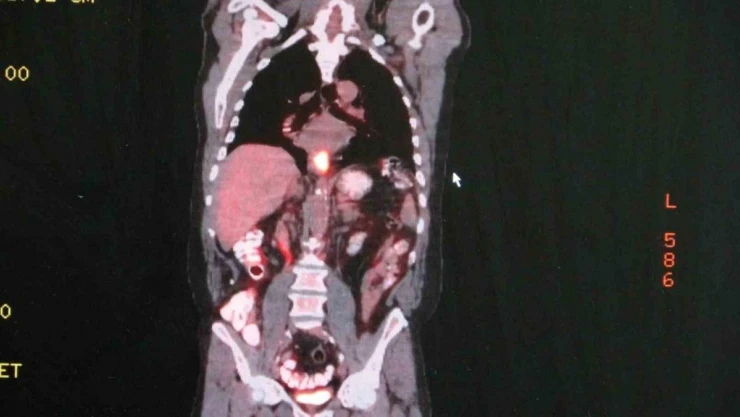

Dünyada en sık görülen kanser türleri arasında 9. sırada olan yemek borusu kanseri hakkında uyarılarda bulunan Marmara Üniversitesi Pendik Eğitim ve Araştırma Hastanesi Göğüs Cerrahisi Anabilim Dalı Doktor Öğretim Üyesi Nezih Onur Ermerak, "Yemek borusu kanseri geç bulgu ve şikayet verdiği için hastalar erken evrede fark edemezler. Hastaların sadece yüzde 25’ini diğer organlara sıçramadan yakalayabiliyoruz" dedi.

Artan yemek borusu kanseri vakalarının ardından hastalıkla alakalı uyarılarda bulunan Ermerak, "Yemek borusu kanseri dünyada 9. sırada en sık görülen kanser tipidir. Ve çok sinsi seyreden bir hastalıktır. Geç bulgu ve şikayet verdiği için genelde hastalar erken evrede fark edemezler. Hastaların sadece yüzde 25’ini diğer organlara sıçramadan yakalayabiliyoruz. Hastalar bu kansere erken evrede yakalandıklarında sağ kalımları yükseliyor. Bu hastalığın semptomları; yutma güçlüğü, yemek yerken takılma hissi, istemsiz kilo kaybı, öksürük, göğüs, iman tahtası ve sırtta özellikle yemek sonrası gelen bir ağrı ve bu gibi şikayetlerle hastalar mutlaka ilgili merkeze başvurmalılar. Erken evrede teşhis hastaların tedavi şansı artmaktadır." dedi.